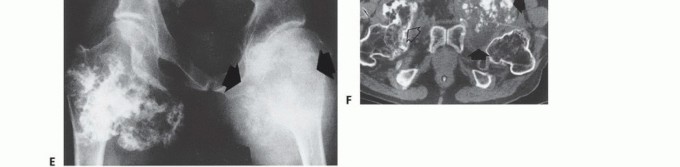

- Plain Radiography: The cornerstone of initial evaluation. It accurately predicts the diagnosis in over 80% of extremity bone tumors. It defines the lesion's location, zone of transition (narrow/sclerotic = benign/slow; wide/permeative = malignant/aggressive), cortical destruction, and periosteal reactions (Codman triangle, onion-skinning, sunburst pattern).

- Computed Tomography (CT): The modality of choice for assessing fine osseous detail, cortical integrity, and matrix mineralization. Thin-slice (≤1 mm) helical CT allows for precise 3D reconstructions. Intravenous contrast is essential to delineate the relationship of the soft tissue mass to major vascular bundles. Chest CT is mandatory for staging to rule out pulmonary metastases.

- Magnetic Resonance Imaging (MRI): The gold standard for evaluating the local extent of the tumor. It accurately defines the intramedullary extent (allowing calculation of bone resection levels), soft tissue extension, joint involvement, and the presence of skip metastases. T1-weighted images best define marrow replacement; T2-weighted and STIR sequences highlight peritumoral edema and the soft tissue mass. Contrast enhancement differentiates cystic from solid components and clarifies neurovascular proximity.

- Bone Scintigraphy (Technetium-99m): Utilized to detect polyostotic disease and skeletal metastases. The three-phase bone scan assesses biologic activity; a "tumor blush" in the flow/pool phases indicates high vascularity typical of malignancy.

- PET-CT (FDG): A functional imaging modality measuring glucose metabolism. It is increasingly the standard of care for total body staging, identifying occult metastases, and monitoring the metabolic response to neoadjuvant chemotherapy (measured by the Standardized Uptake Value, SUV).